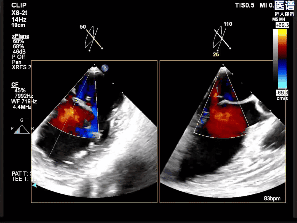

术中影像

房间隔穿刺

置入瓣膜夹

第一次关闭瓣膜夹

超声提示仍存在少量反流

第一次夹合后3D

第一次夹合后3D彩

调整瓣膜夹位置

再次捕获瓣叶

第二次关闭瓣膜夹

测量前后瓣距离

释放夹子

夹子释放后反流降至轻度

3D下组织桥稳定

3D下上彩

术后平均压差为4mmHg